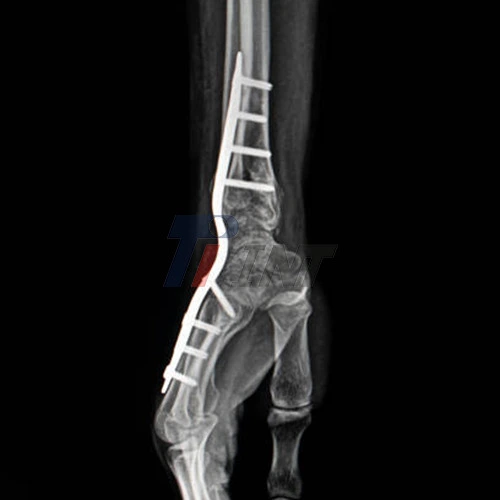

Titanium, a biocompatible metal known for its strength-to-weight ratio and corrosion resistance, has revolutionized the approach to treating complex wrist fractures. The use of titanium plate for wrist fractures has gained widespread acceptance among orthopedic surgeons due to their ability to provide stable fixation while minimizing the risk of complications.

The evolution of titanium plate design has been driven by a deep understanding of wrist anatomy and biomechanics. Modern titanium plates are engineered to match the contours of the distal radius and ulna, allowing for precise placement and optimal load distribution. This anatomical design, coupled with titanium's inherent properties, has significantly improved the outcomes of wrist fracture surgeries.

- Radiolucency: Titanium is relatively radiolucent compared to other metals, allowing for better visualization of the fracture site on X-rays and CT scans. This property facilitates easier post-operative monitoring and assessment of fracture healing.